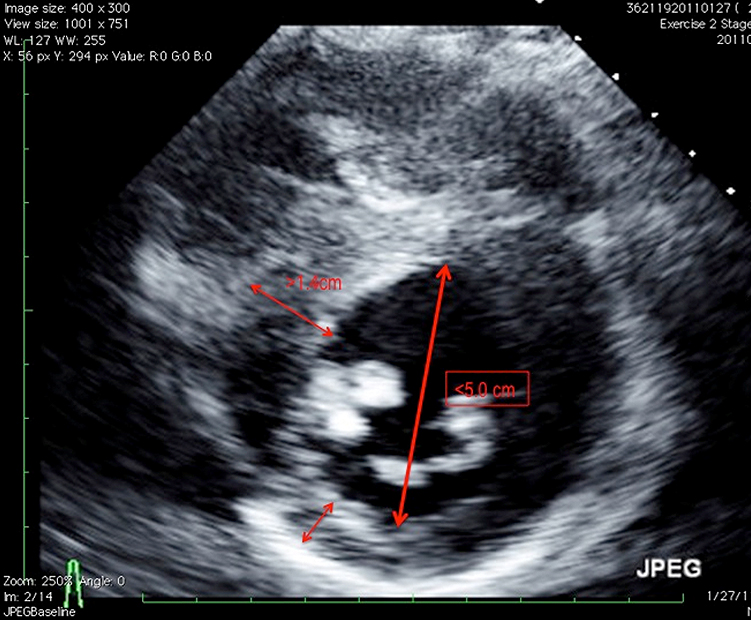

A 19-year-old college athlete with prior diagnoses of a bicuspid aortic valve and an "athletic heart" is scheduled to leave for tryouts for a professional soccer team in Spain. Independent review of his electrocardiogram (ECG) (Figure 1) prompted a closer look at his last evaluation by his pediatric cardiologist. The echocardiogram showed mild AS from a bicuspid valve aortic valve without aortic dilatation (Figures 2 and 3). His left ventricular cavity was small with abnormal papillary muscle size and position (Figure 4). Cardiac magnetic resonance imaging (MRI) was suggested and showed findings similar to the echocardiogram (Video 1); in addition there was delayed enhancement suggestive of fibrosis (Video 2). A stress test was performed, and a 3 beat run of ventricular tachycardia (VT) occurred in stage five (Figure 5). He was restricted from competitive sports and first-degree relatives were evaluated. No gene mutation was identified. His father was screened. Although he had no evidence of aortic valve disease or aneurysm formation, the patient was diagnosed with hypertrophic obstructive cardiomyopathy (HOCM) and was restricted from playing competitive soccer.